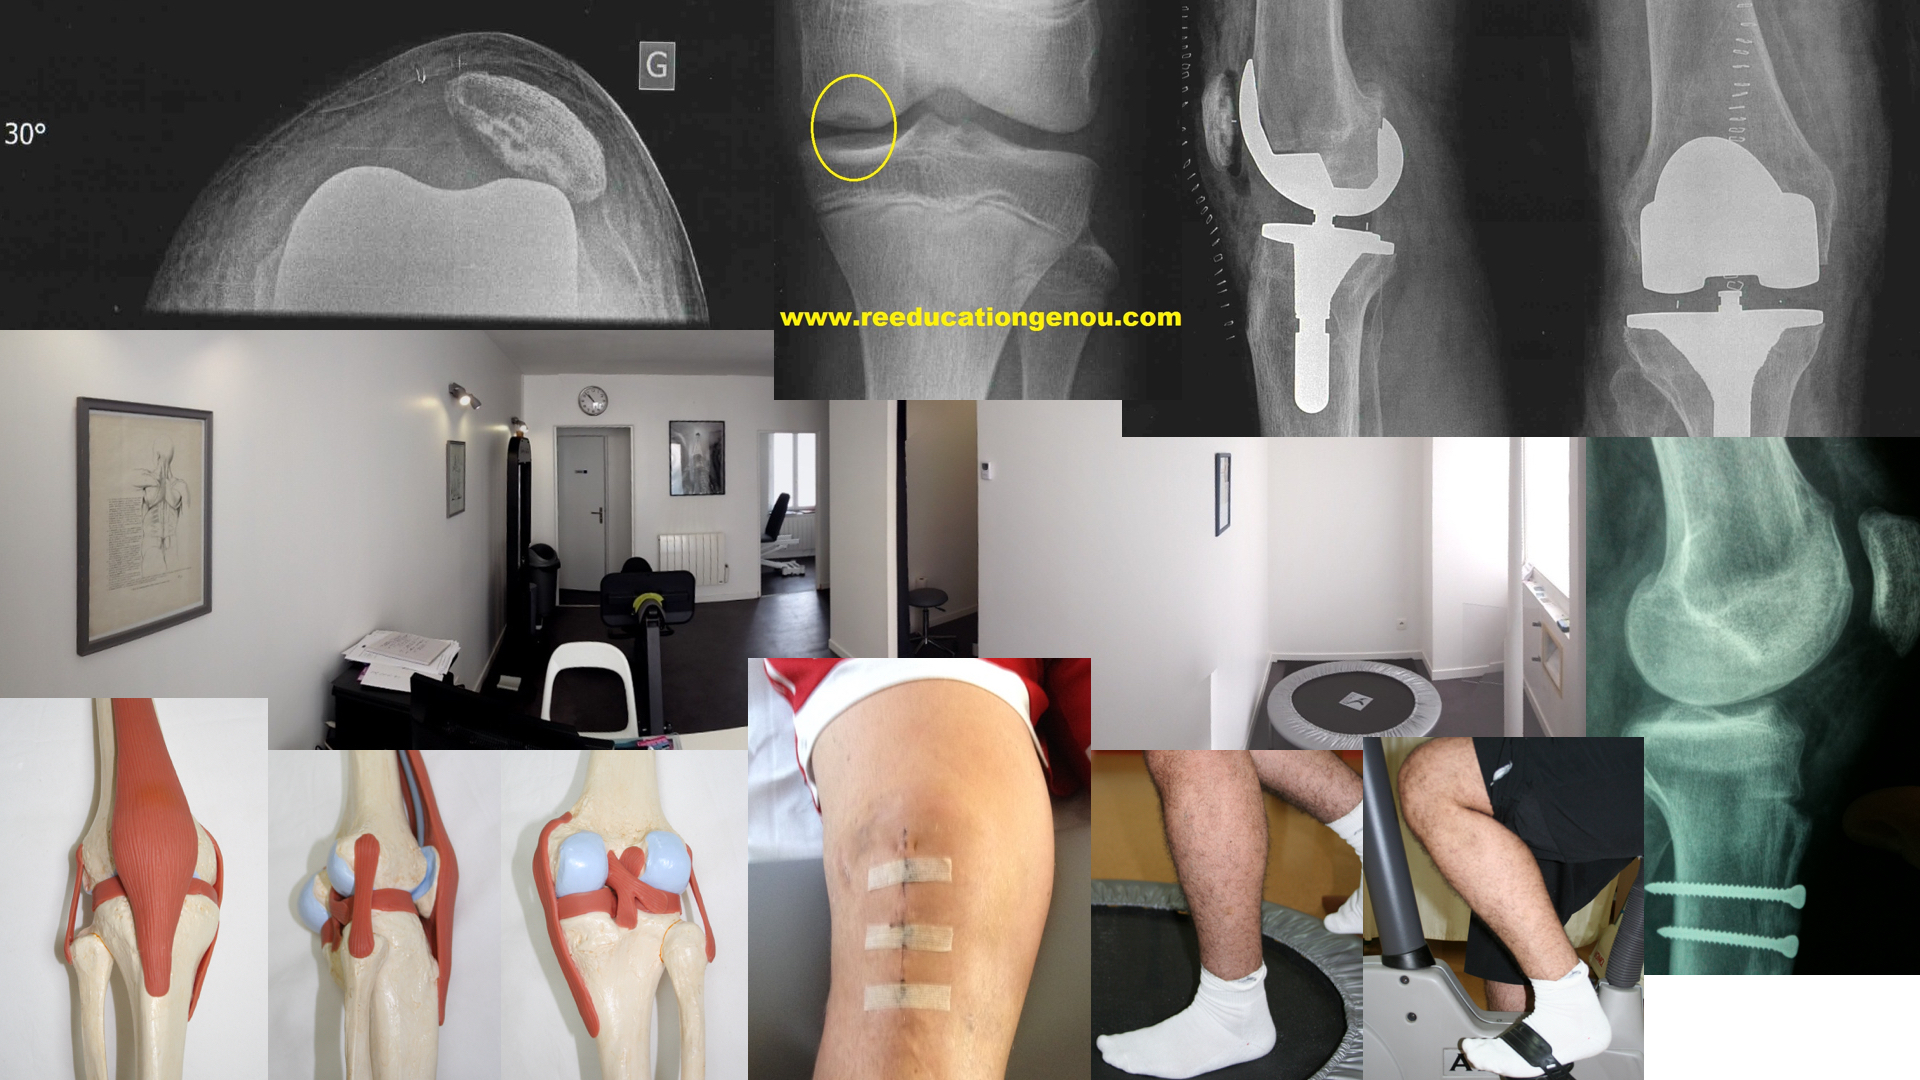

photo d'un TLS avec les vis en titane (désormais les vis sont en calcium)